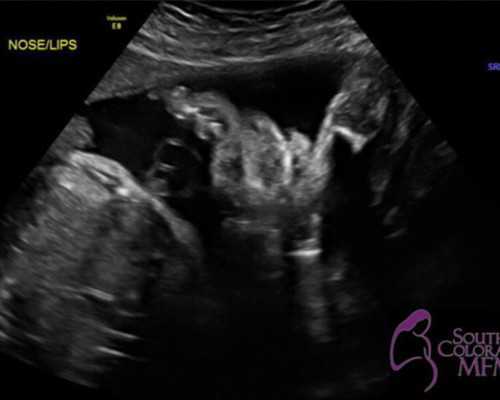

2. 卵子采集:在卵子发育到一定程度后,使用超声引导下的细针将卵子采集出来。